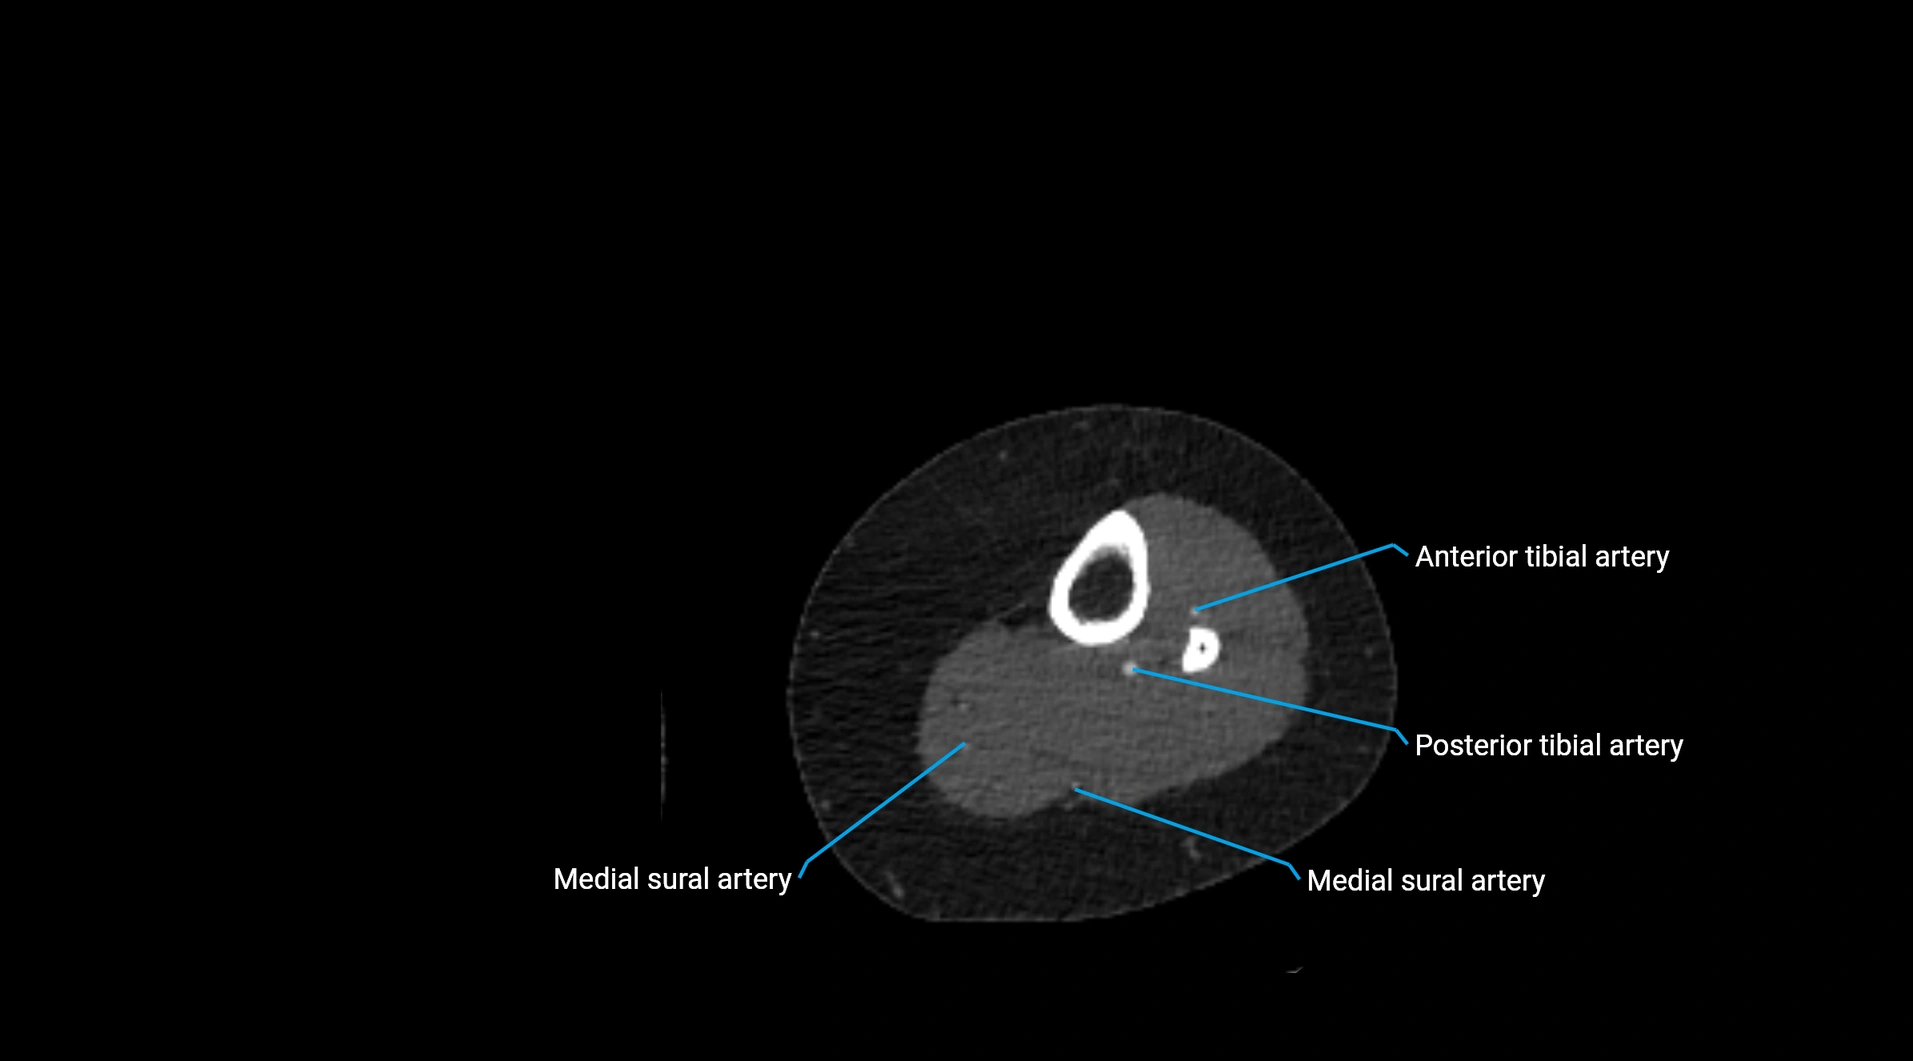

CT images

image

Contrast-enhanced CT (CTA):

• Gold standard for abdominal aortic imaging

• Provides excellent detail of lumen, wall, aneurysm, thrombus, and branch vessels

• Multiplanar and 3D reconstructions help in aneurysm measurement, stent graft planning, and dissection evaluation